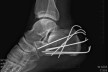

Ještě ten den večer jdu na sál. Zlaté ruce Fildy za hodinu spletli na mé patě ze sedmi drátů klec, něco jako když se o Velikonocích splétá pomlázka a uvěznili v něm ježka. Respektive myšlenku mi vnukl až pohled přes rameno na rentgenový snímek s daným výtvorem a samolibě spokojeného umělce. Celý akt té řezničiny byl zakončen hlubokým hlasem Alfa samce s rouškou na tváři, v podobě pochvalné ódy na sebe sama a slovy, „Fakt se mi to povedlo.“

Vážné zranění narušilo plány Marka Holečka který se letos chystal na Gašerbrum I, vypadl nešťastně pod druhým kruhem na známé prachovské cestě spadl ze skály z výšky osmi metrů a rozdrtil si nějaké kosti v patě. Ve čtvrtek se podrobil operaci, v noze má sedm drátů a několik zpevňujících šroubů. Sezona tak pro něj nejspíš skončila.